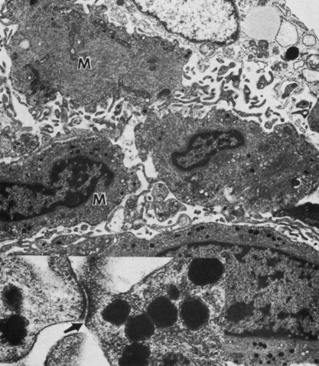

Fibroblasts are prominent on the iris surface. Transmission electron microscopic examination of these fibroblasts reveals abundant mitochondria, rough endoplasmic reticula, free ribosomes, and bundles of filaments (Fig. 9). Some fibroblasts have basal bodies in their cytoplasm, with associated cilia projecting into the anterior chamber (Figs. 10 and 11). Melanocytes are most often found just beneath fibroblasts and contain mitochondria, smooth and rough endoplasmic reticula, free ribosomes, and melanin granules in various stages of development (Fig. 12). The blood vessels and nerve fibers of the anterior border layer are similar to those in the deeper stroma and are discussed later.29

Fig. 9. The anterior border of the iris is composed of a discontinuous layer of fibroblasts (F) and interspersed collagen fibrils (arrows) (×13,800). Inset shows fibroblasts and a meshwork of collagen connecting fibroblasts (×40,500).

Fig. 12. Inset shows a junctional complex (arrow) forming the anterior border layer of the iris (scanning electron microscopy, ×1500). Melanocytes (M) are present beneath the fibroblasts (F) of the anterior border layer (×10,500).